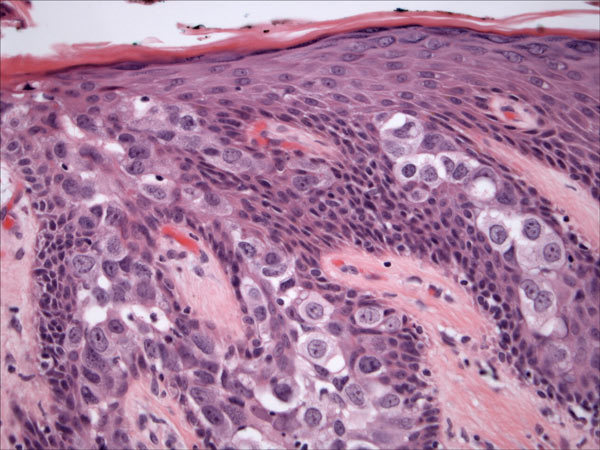

Paget’s disease of the nipple

DDx

Paget’s

Toker cells

Squamous cell carcinoma in situ/Bowen’s disease

Melanoma

Best 4 stains (all negative in Paget’s)

HER2 is the most useful single immunostain